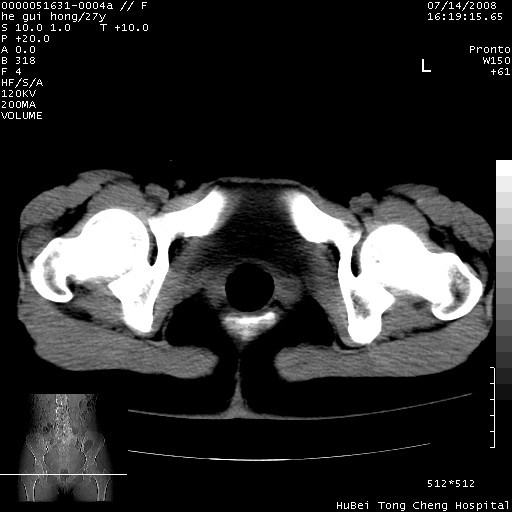

以下是引用杀毒软件在2008-7-20 8:03:00的发言:[br]支持双侧卵巢囊腺瘤可能性大!

以下是引用zjzjr在2008-7-20 13:36:00的发言:[br]双侧附件囊腺瘤可能性大!